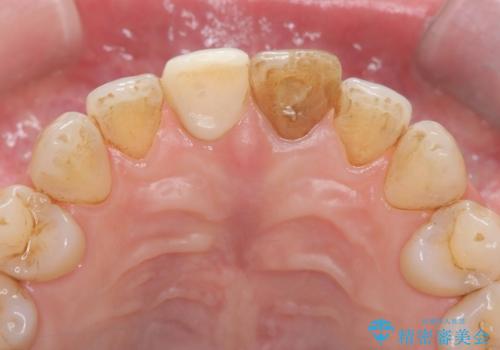

- 気を失って転倒し、前歯をぶつけたことをきっかけに「かかりつけ医で抜歯と診断された」との主訴で来院された患者様です。

レントゲン撮影や顕微鏡下での精査、メチレンブルーによる染色検査を行った結果、破折線は認められず、保存可能と判断しました。

精密根管治療を行い、その後オールセラミッククラウンで審美的に修復しています。あわせてホワイトニングとエアフローによるクリーニングも行い、自然で美しい仕上がりとなりました。